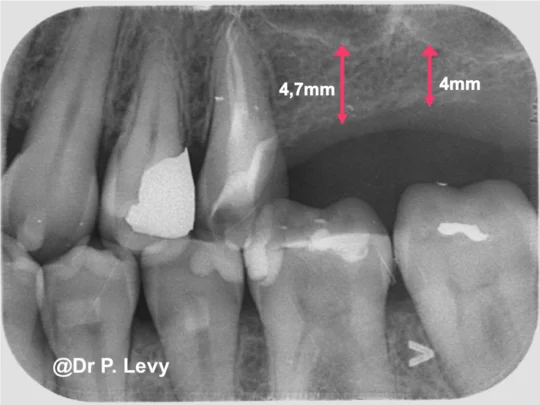

L’examen clinique et radiologique montre une crête édentée d’une bonne largeur mais dont la hauteur est insuffisante pour la pose d’implants (entre 4 et 5mm mesurée sur le cone beam)